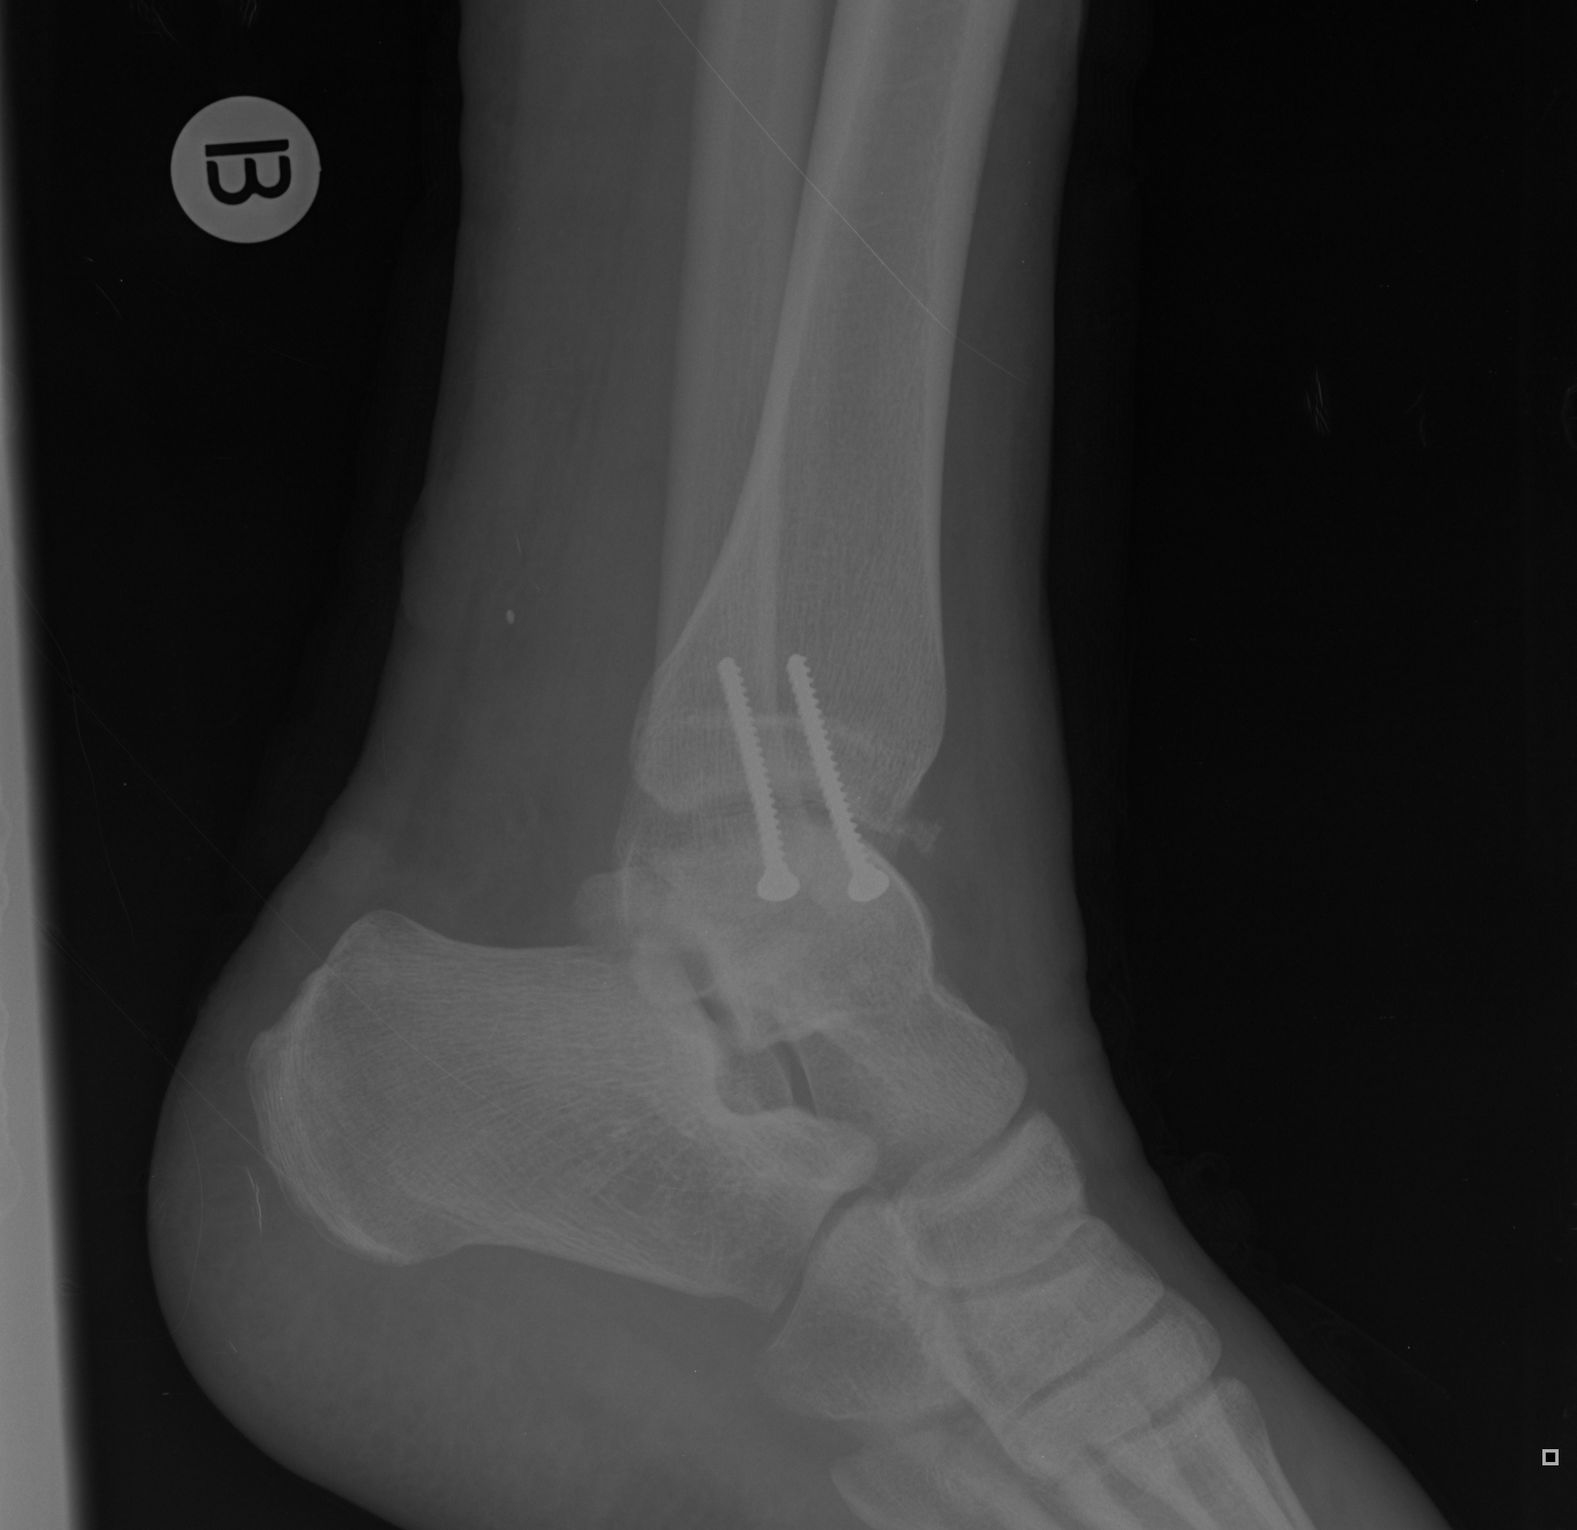

Nyílt combcsont- és bokatörés volt a két legsúlyosabb. Ami maradt:

- a combcsontomnál hiányzik egy tenyérnyi izom, a nyílt törés miatt roncsolódott, ki kellett dobni;

- a bokám nem hajlik előre-hátra teljes mértékben (sétával, biciklizéssel, motorozással nincs gond, de guggolni pl. nem tudok);

- hegek (egyértelmű);

- és hamarabb elfárad a lábam.Azt kell mondjam, hogy ahhoz képest nem olyan vészes, jó munkát végeztek a dokik és a gyógytornászok.